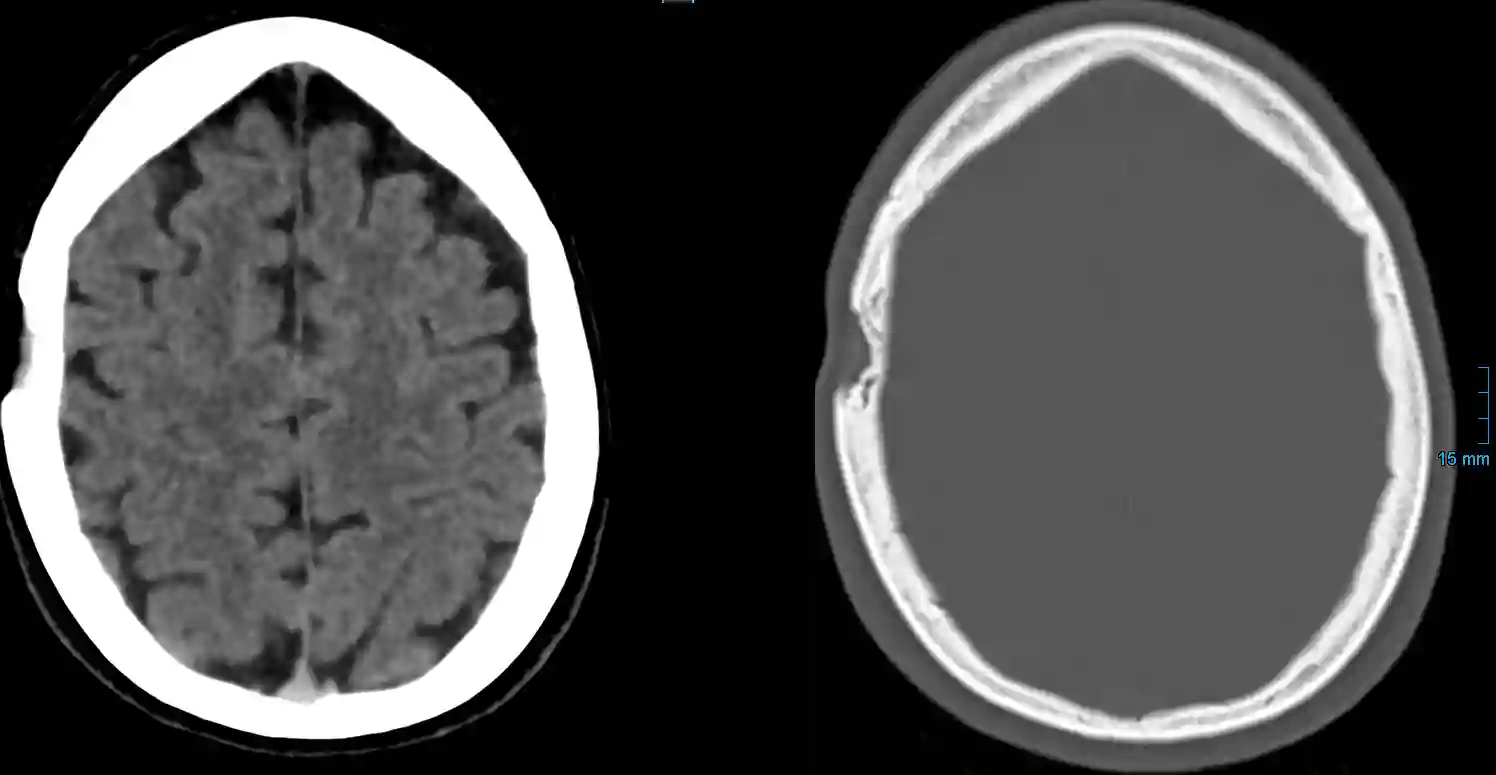

Am Schädel kann man je nach Morphologie drei verschiedene Typen der fibrösen Dysplasie unterscheiden7:

- Zystisch (Wobei hier nicht zystisch im klassischen Sinne gemeint ist): Erweiterung der Diplöe mit Ausdünnung der Tabula externa und wenig Involvierung der Tabula interna. Kommt typischerweise an der Schädelkalotte vor.

- Gemischt: Die Läsion zeigt sich ähnlich dem zystischen Typ mit Anteilen an erhöhter Densität in der Läsion.

Bildgebung

Läsionen einer fibrösen Dysplasie lassen sich im MRT oder in der CT Bildgebung darstellen.